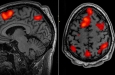

Измерение дофамина в реальном времени

Исследователи измерили активность мозга у мышей, когда они нажимали на утяжеленный рычаг, включая и выключая дофаминовые клетки с помощью светового метода.

Если бы быстрые всплески дофамина действительно контролировали бодрость, изменения дофамин в этот момент должен был совершать движения быстрее или медленнее. К их удивлению, это не оказало никакого эффекта. В ходе испытаний с леводопой они обнаружили, что лекарство действует за счет повышения базового уровня дофамина в мозге, а не за счет восстановления быстрых всплесков.